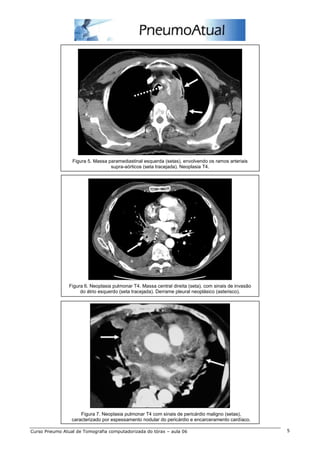

Figura 5. Massa paramediastinal esquerda (setas), envolvendo os ramos arteriais

supra-aórticos (seta tracejada). Neoplasia T4.

Figura 6. Neoplasia pulmonar T4. Massa central direita (seta), com sinais de invasão

do átrio esquerdo (seta tracejada). Derrame pleural neoplásico (asterisco).

Figura 7. Neoplasia pulmonar T4 com sinais de pericárdio maligno (setas),

caracterizado por espessamento nodular do pericárdio e encarceramento cardíaco.